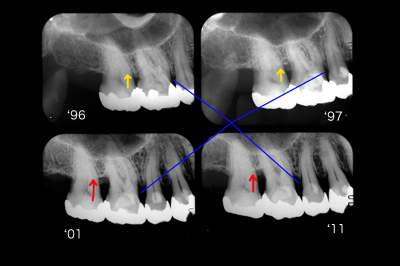

30代後半女性(当時)。右上6周囲のアタッチメントレベルは'96~'97に大差ありません(黄矢印)。ところが'01で大きな変化が現れました(赤矢印)。4年の間に生活に大きな変化がありそれが引き金となって夜間就寝時に自分で自覚するほどの強い歯ぎしりをするようになったとのことでした。ナイトガードの使用と自己暗示療法を開始しました。

いずれも奏功しアタッチメントロスは停止したようです。'01~'11まで変化なく骨レベルは安定しています。